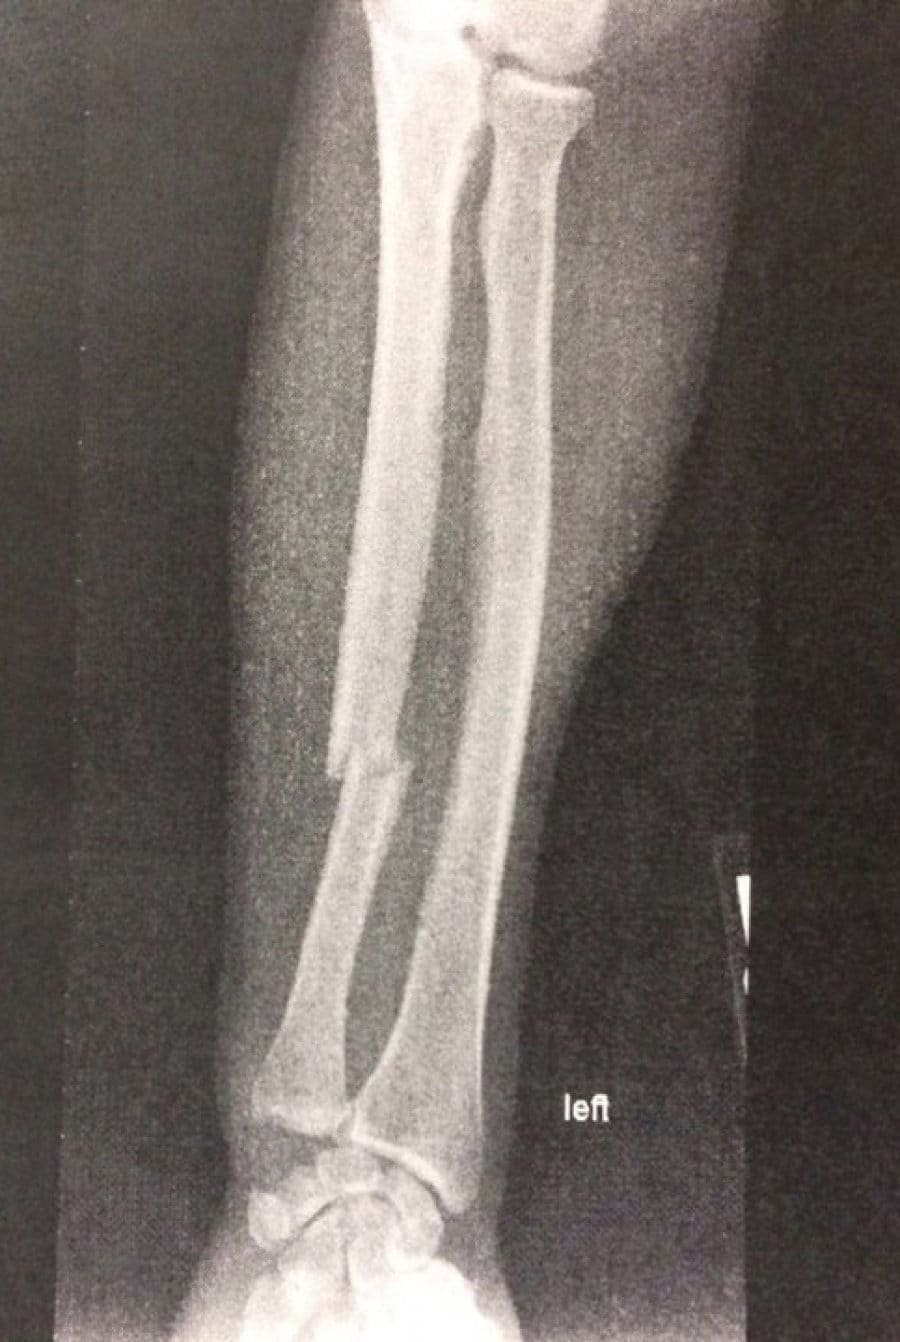

Холли Холм, завоевавшая титул Legacy FC в легчайшем весе в поединке с Джулианой Вернер, сломала левую руку во время боя. По информации ресурса Southwest Fight News, бывшая чемпионка мира по боксу получила травму уже в ранних раундах, что заставило ее меньше работать руками и больше подключать ноги. В результате, в пятом раунде Холм опрокинула соперницу хай-киком на настил и провела добивание. После медицинского обследования Холли Холм представила в Facebook рентгеновский снимок, подтверждающий наличие травмы.